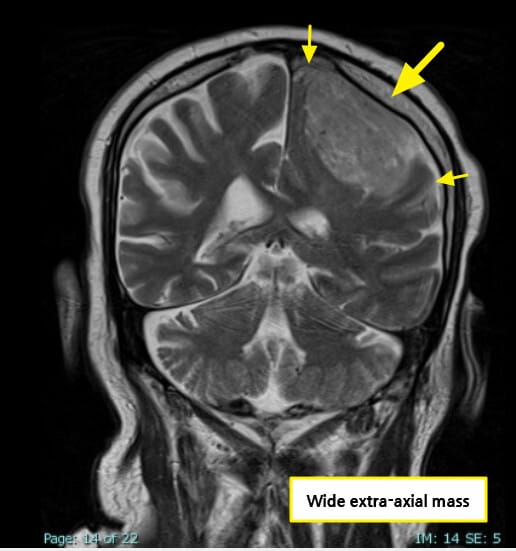

영상소견

조영 증강 MRI에서 경막에 붙어 자라는 균일한 종괴가 보입니다.

| Meningioma 영상소견 |

| 🔵 조영 증강 종괴 + Dural tail sign |

| 경막을 따라 꼬리처럼 조영되는 소견으로 수막종의 대표 영상 특징입니다. |